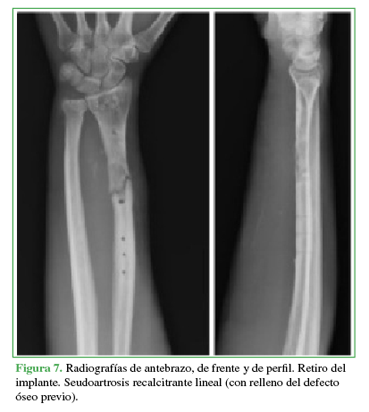

En consecuencia, se procedió a una nueva intervención para retirar el implante, explorar el foco, tomar muestras bacteriológicas y para la estabilización externa con yeso (Figura 7).

Ante los resultados negativos de las muestras de tejido enviadas a bacteriología y la seudoartrosis recalcitrante de radio, se realizó una nueva intervención con revisión y desbridamiento fibroso del foco óseo, estabilización con placa recta de 3,5 mm de diámetro y relleno con injerto óseo molido alógeno del banco de tejidos (Figura 8).